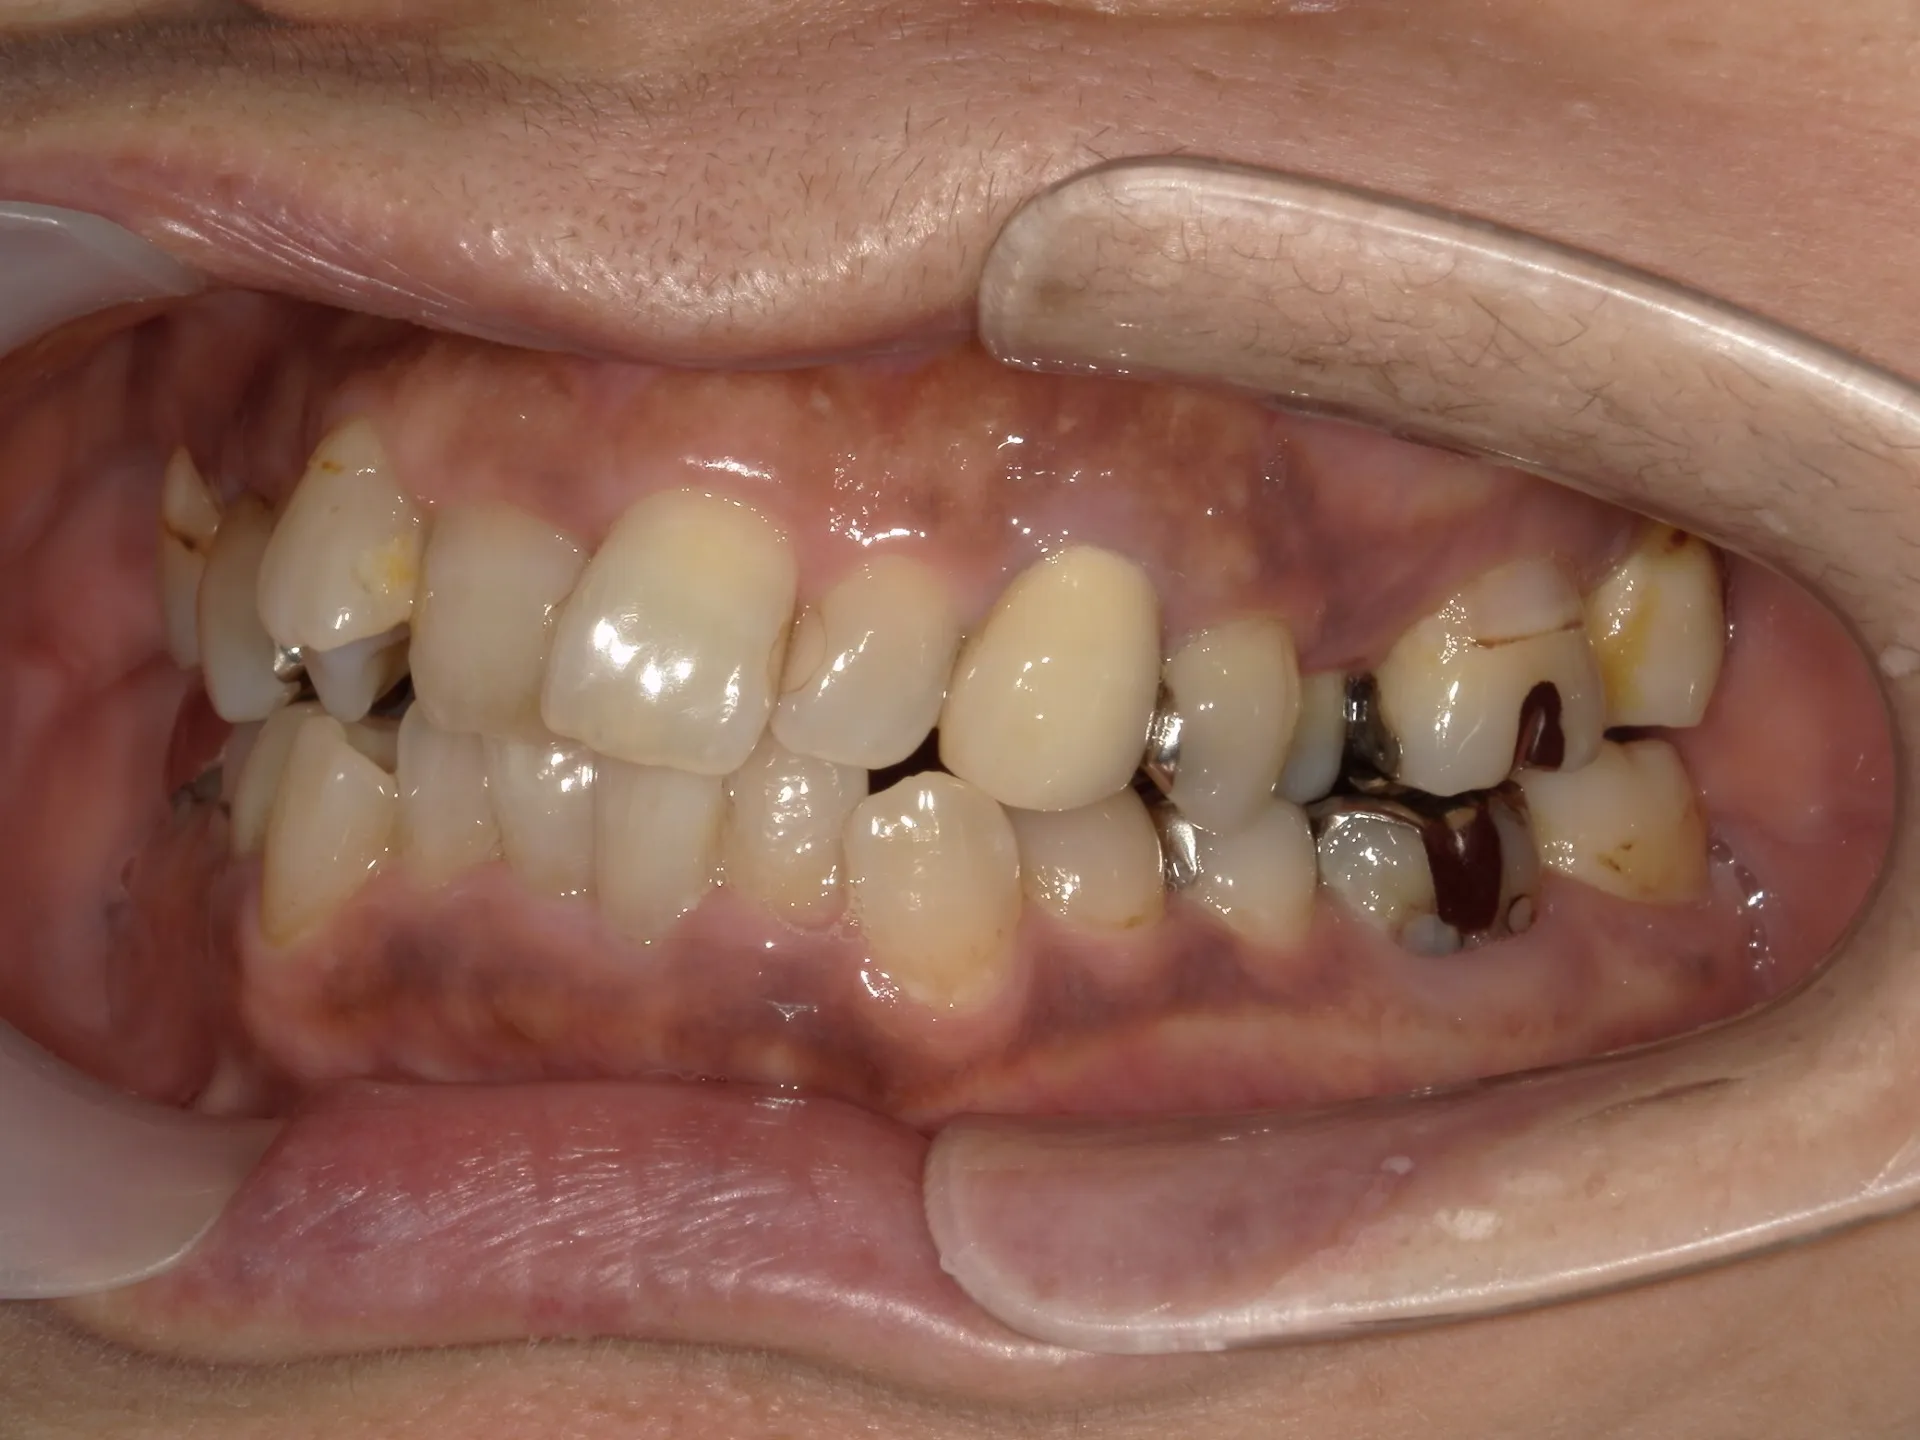

今回は65歳以上でも矯正治療を開始した症例についてご紹介いたします。

しかし、年齢がたとえ定年を迎えたあとであっても十分に矯正が行えて、今後の歯磨きが容易になり、虫歯や歯周病のリスクが減らせて歯を残すことが出来たり、歯並びが良くなったことでモチベーションも上がるなどの矯正後のメリットも非常に高いため、健康的な生活を行う上でも矯正治療は行うことをお勧めします。